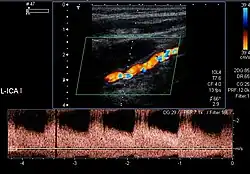

| Objaw „sznura pereł” w kolorowym doplerze u 51-letniej kobiety z zawężającą FMD wewnętrznej tętnicy szyjnej niskiego stopnia. |

| Ten sam przypadek; dopler spektralny pozwala ocenić zwężenie lewej tętnicy szyjnej na około 70%. | ![]() |